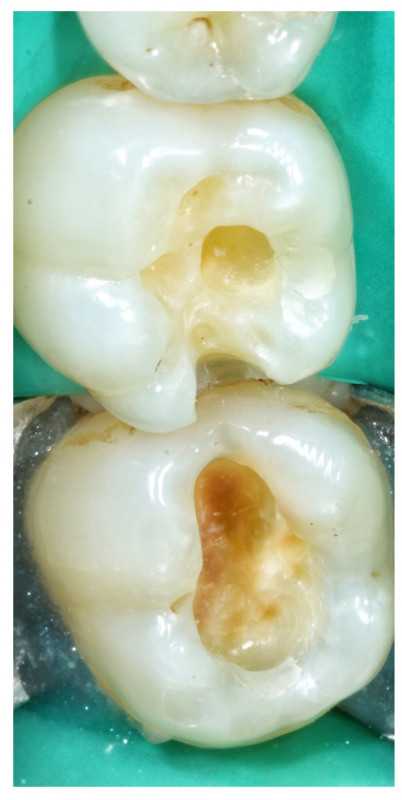

3 работы в портфолио

Серков Евгений Владимирович принимает в стоматологической клинике ЛАГУНА СТОМ в Москве. Стаж 9 лет. Специализируется на терапевтии и хирургии, по которым клиника оказывает 21 услугу. Имеет 3 работы до/после в портфолио. Квалификация специалиста подтверждена 3 лицензиями, сертификатами и наградами. Для уточнения дополнительной информации о специалисте или записи на прием можно позвонить по телефону